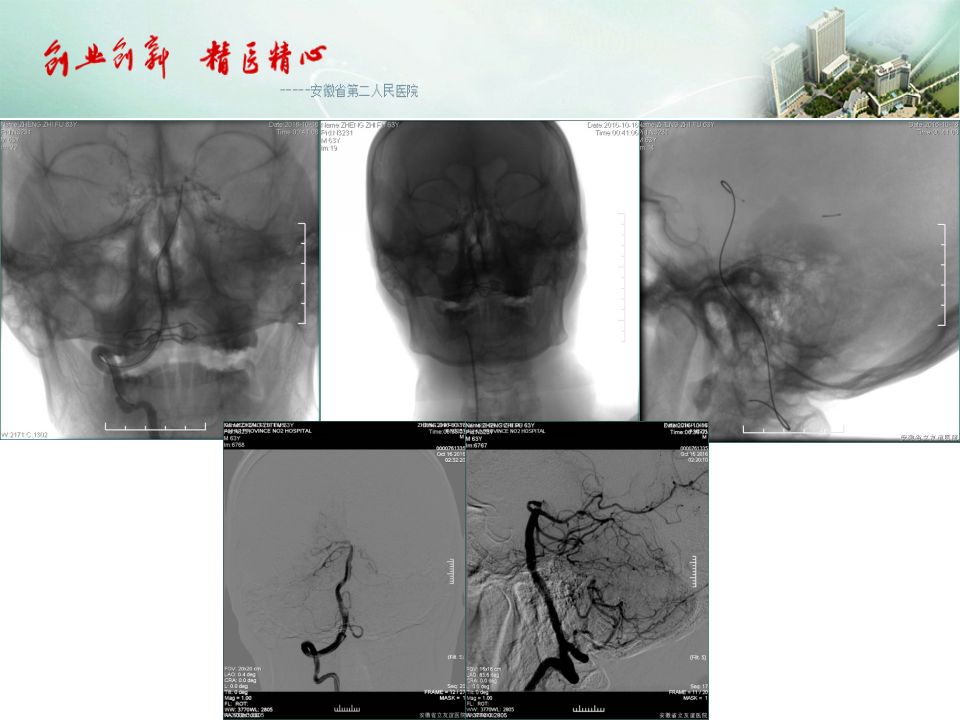

今天为大家分享的是“强生医疗CNV-神经介入专栏”第五十一期,由安徽省第二人民医院神经内科陈长春主任医师带来的“急性缺血性脑卒中超早期治疗--通与不通的哲学思考”精彩PPT,欢迎观看。文章仅代表作者个人观点,如有不同见解,欢迎同道斧正!